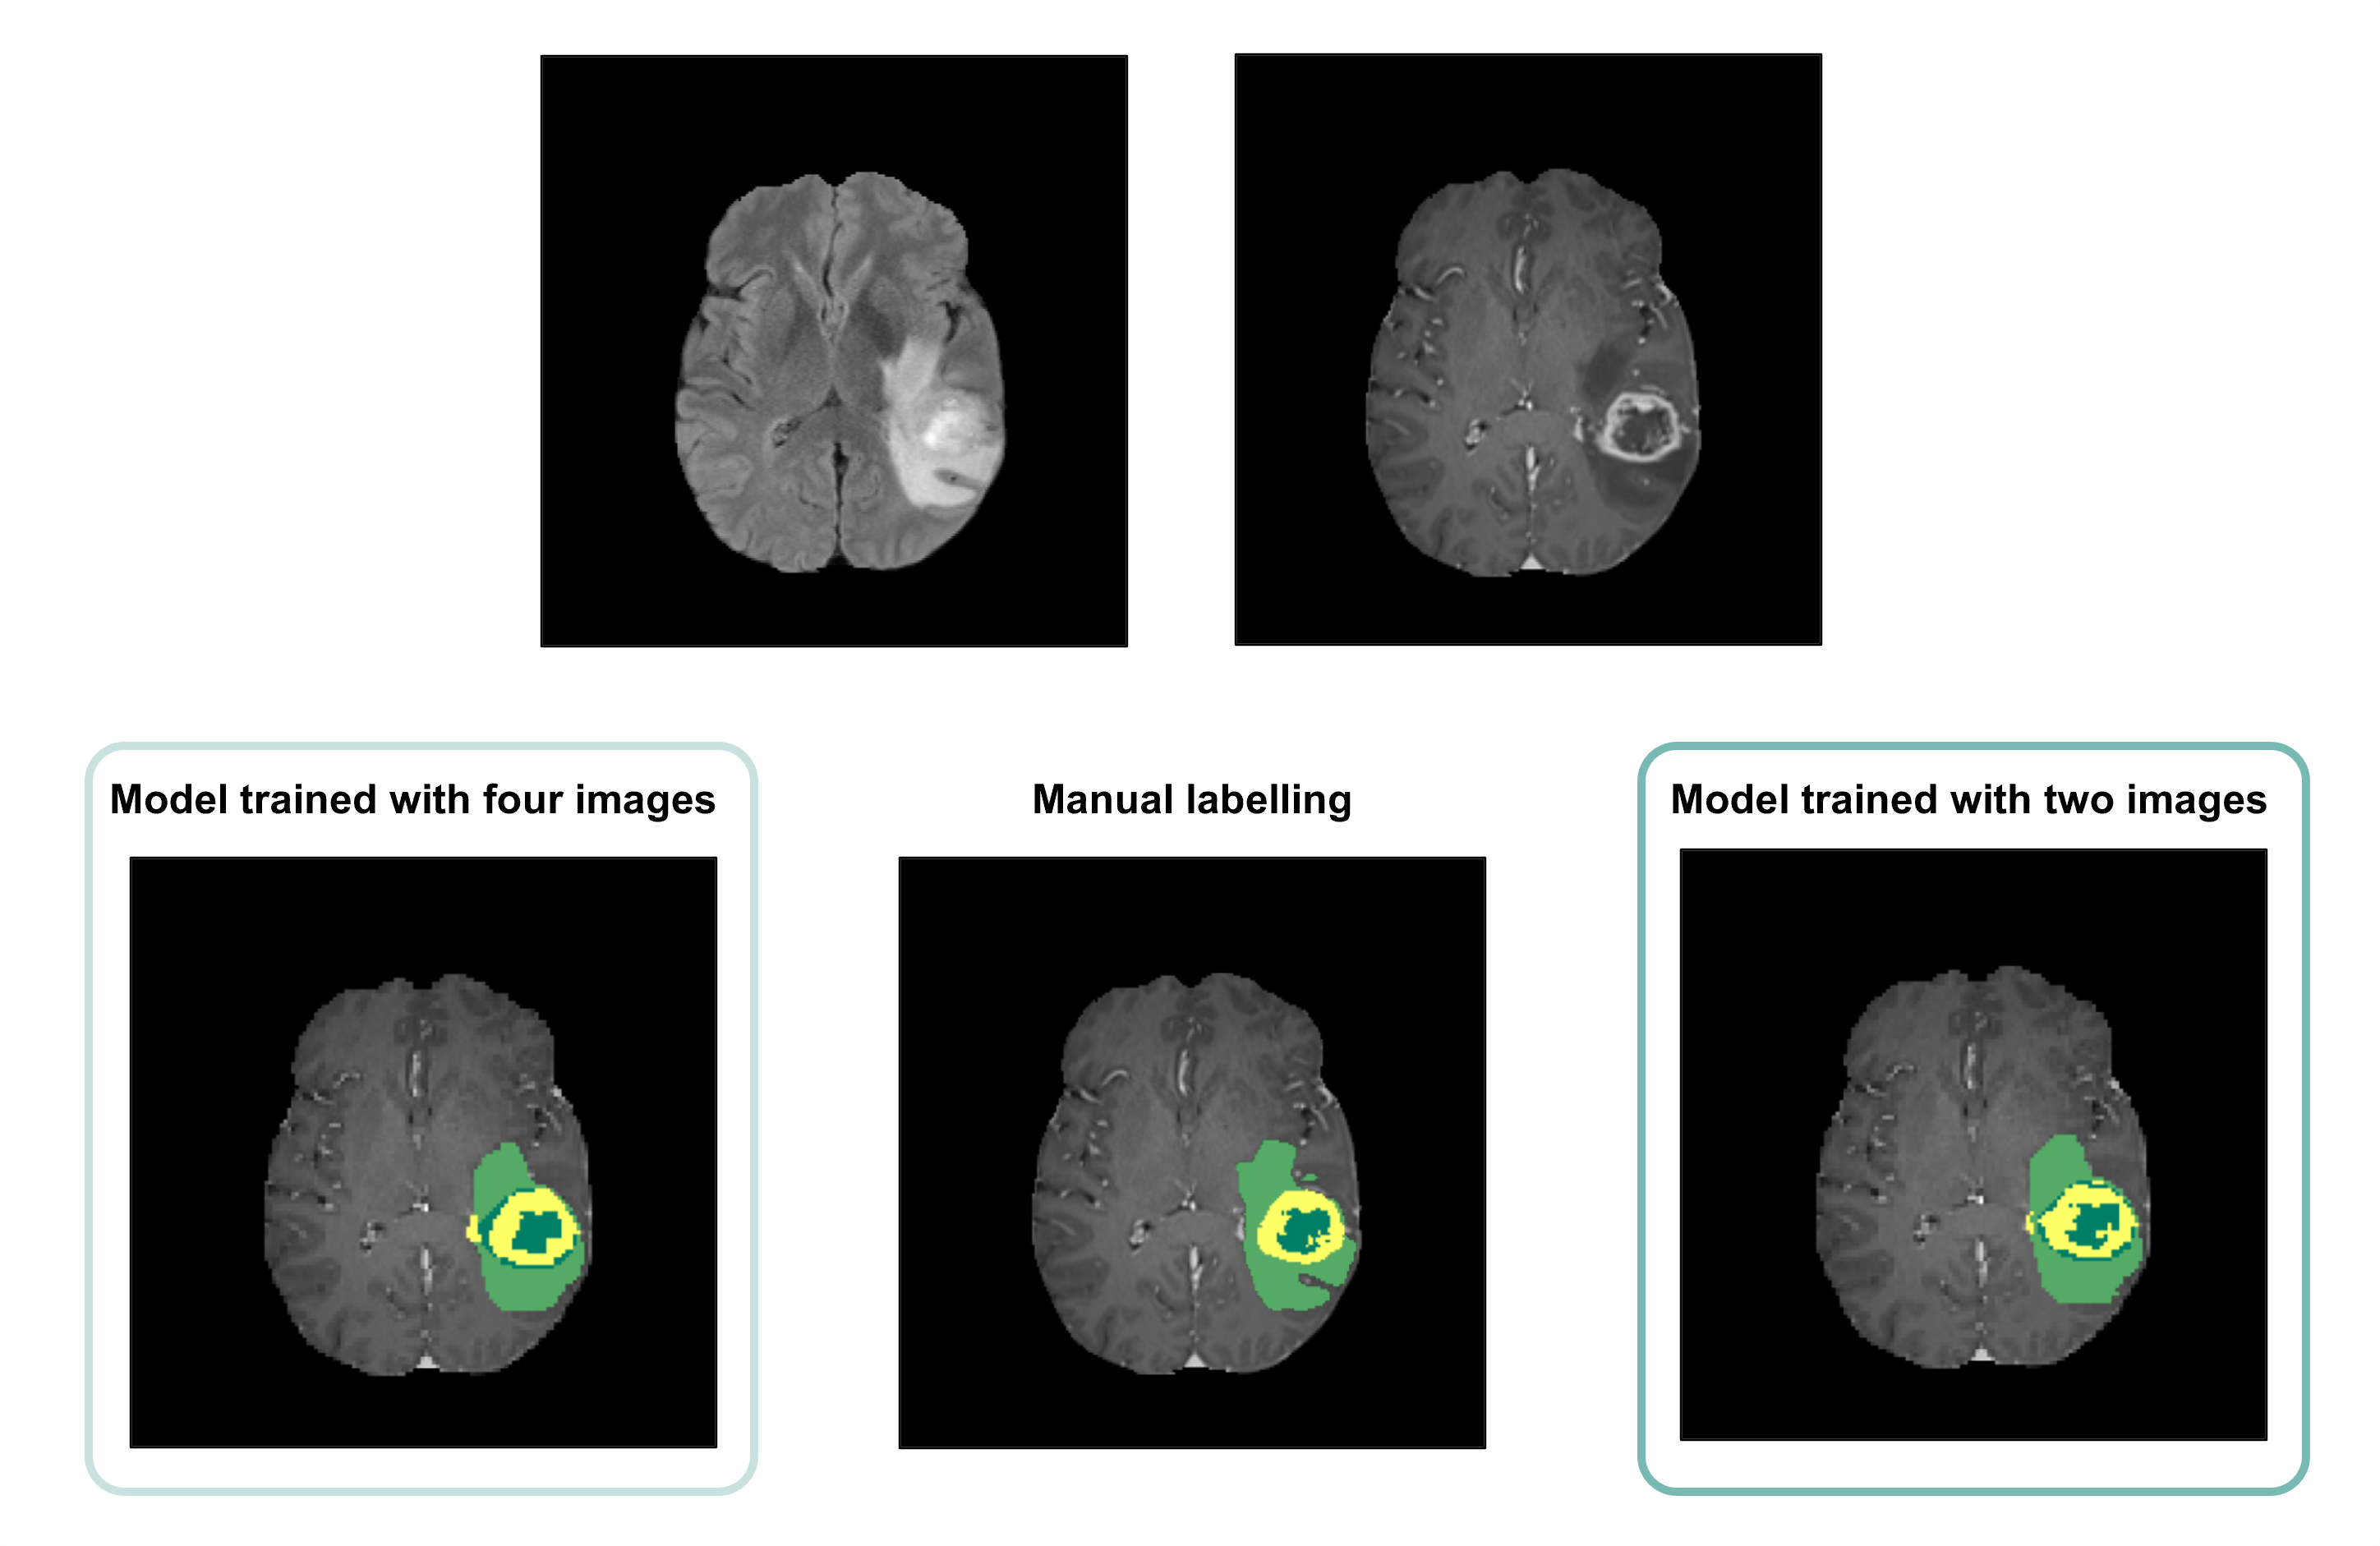

Average Dice scores obtained with the two training approaches are presented in Table 1 and Figure 2. The results corroborate the selected combination of segmentation outputs from the two networks. The segmentation accuracy when training with FLAIR and T1ce images was consistent with the performance when training with four modalities, showing slightly higher values for the WT and TC regions. Wilcoxon signed-rank tests revealed statistically significant differences between the models for these regions (p-values<0.001). In Figure 3, the manual segmentation can be visually compared to the two outputs obtained for a representative subject.

Figure 3: Top - Representative slice from the original (left) FLAIR and (right) T1ce images from one of the subjects included in the testing dataset. Bottom - Comparison between the output segmentation obtained with the two models and the respective manual segmentation included in the BraTS2021 public dataset. The lighter green, yellow and darker green colours correspond to the WT, ET and TC regions, respectively.